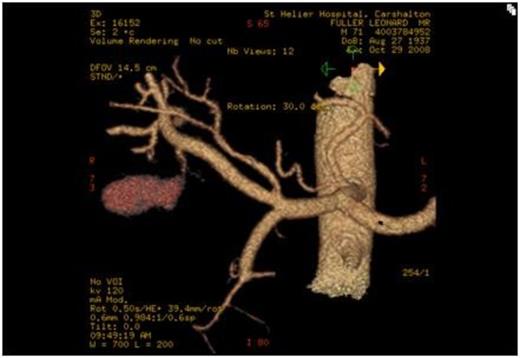

The next step was for embolisation of the CAP. A transfemoral approach was employed and a microcoil placed successfully in the cystic artery (Fig. 2). A right sub-hepatic drain was placed, which drained a total of 1130ml of dark inflammatory fluid, in the first 24 hours. The patient clinically improved over the next 7 days, his inflammatory markers normalised and the drain was removed when dry. The patient was discharged home and laparoscopic cholecystectomy was arranged electively.